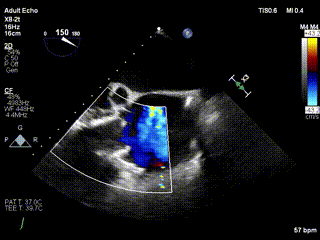

2021年12月24日,復(fù)旦大學(xué)附屬中山醫(yī)院葛均波院士團(tuán)隊成功應(yīng)用LuX-Valve Plus為一例極重度三尖瓣反流(TR)合并房顫、房缺的患者完成了經(jīng)血管三尖瓣置換術(shù),這是在前基礎(chǔ)上,本周完成的第三例經(jīng)血管三尖瓣置換手術(shù),葛均波院士、周達(dá)新教授等與心外科魏來教授、賴顥教授,心超室的潘翠珍教授、李偉教授及麻醉科的郭克芳教授共同完成了本周手術(shù),均獲得圓滿成功!患者術(shù)后超聲顯示無TR,臨床癥狀明顯改善。本周手術(shù)的成功也為LuX-Valve Plus救治性臨床研究添上了濃墨重彩的一筆。

三例患者入院后,葛均波院士團(tuán)隊周達(dá)新教授、潘文志教授、張源博士、陳莎莎博士及心超室的潘翠珍教授、李偉教授對患者的情況進(jìn)行詳細(xì)評估和討論,最終決定為三例患者選擇LuX-Valve Plus40mm、50mm和50mm型號的瓣膜進(jìn)行手術(shù)治療。手術(shù)后即刻拔除氣管插管,術(shù)后患者三尖瓣反流癥狀得到顯著改善,復(fù)查心超結(jié)果顯示人工三尖瓣瓣膜支架固定穩(wěn)定,瓣葉關(guān)閉形態(tài)未見異常,未見明顯反流。